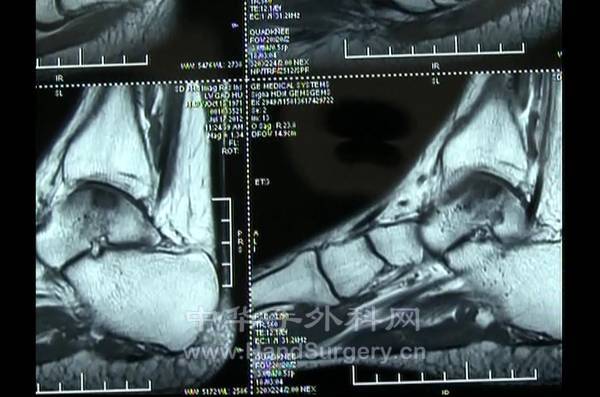

昨天参观了一台手术

距骨坏死,马赛克植骨

共同分享学习

20.jpg